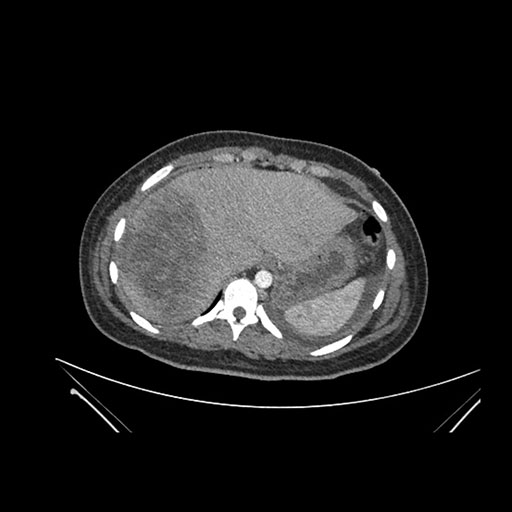

Axial Arterial

Axial Venous

Coronal Arterial

Coronal Venous

Imaging analysis

Based on initial findings, which issue(s) would you be most concerned about?